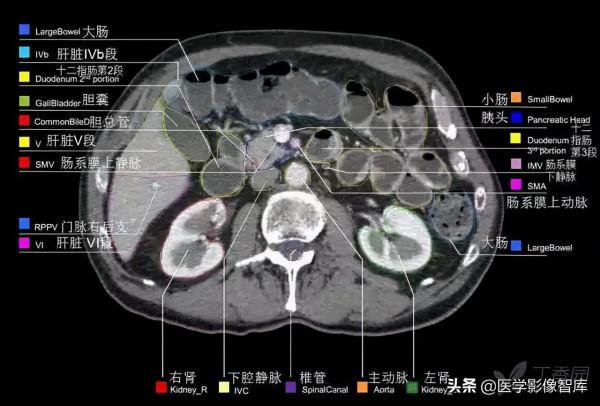

腹部CT